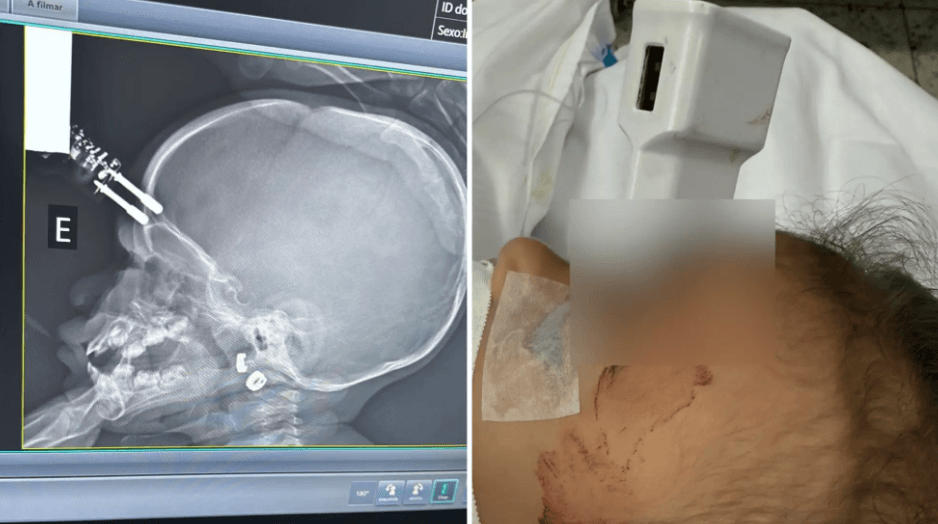

Um carregador de celular ficou cravado na testa de uma criança de 1 ano e seis meses após uma queda da cama, em Divinópolis, no Oeste de Minas Gerais. A menina foi levada às pressas para o hospital e passou por cirurgia de urgência na segunda-feira (12/1).

O objeto perfurou a região frontal do crânio, próxima ao olho. A criança foi encontrada no chão do quarto com sangramento, após a mãe ouvir o choro pela manhã. O Samu fez o resgate e encaminhou a menina ao Hospital São João de Deus.

Exames apontaram que o pino do carregador atravessou a calota craniana. A equipe médica realizou a retirada do objeto, limpeza e reconstrução da área atingida. O procedimento ocorreu sem complicações.